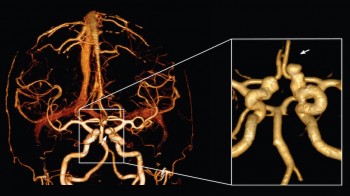

Šta je CT koronarografija?

To je metoda prikaza malih arterija koje hrane  srčani mišić, upotrebom CT skenera, koji prikazuje protok krvi u koronarnim arterijama i kompjuterskog softvera da bi se dobio odgovarajući trodimenzionalni prikaz. CT angiografija je neinvazivni način da se prikažu zidovi koronarnih arterija I nadju eventualni aterosklerotski plakovi, što pomaže liječniku u odredjivanju rizika srčanog udara.